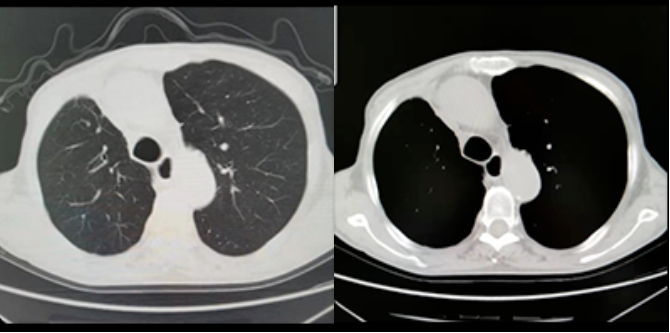

随诊:2020年7月17日胸部CT(图1)右中肺新发小结节,考虑转移。

图1.2020年随诊胸部CT

随诊:2021年1月3日胸部CT:右中肺结节增大,考虑转移。

图2. 2021年随诊胸部CT